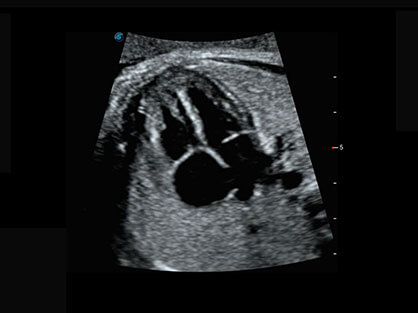

宽频带腹部凸阵探头和腹部容积探头、大角度腔内探头和腔内容积探头、独特的生殖专用曲柄探头,为妇产应用提供全面诊疗方案。

大角度腔内容积探头,可完整包络子宫及盆底结构,充分展示组织结构毗邻关系。